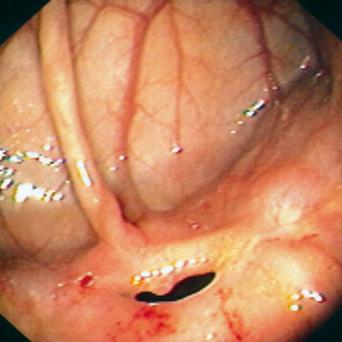

La stéatopathie métabolique est devenue la première cause de maladie chronique du foie. Le risque principal est la fibrose, qui, lorsqu’elle est sévère, peut évoluer vers une cirrhose et un carcinome hépatocellulaire. Qui faut-il dépister en soins primaires et comment interpréter les résultats ? Quelles options thérapeutiques ont fait leurs preuves ? Que peut-on attendre des nouvelles molécules ? Le point avec le Pr Stanislas Pol, hépatologue, hôpital Cochin, Paris.